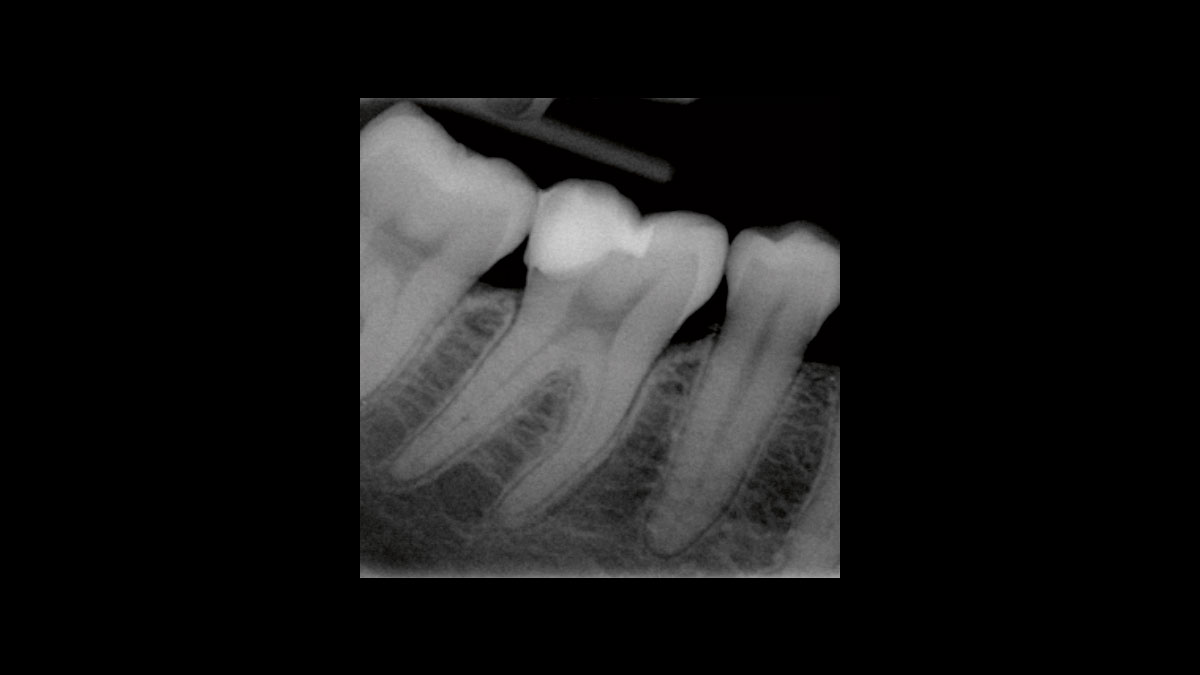

Diode Laser Implant Uncovery . This study was designed to assess if dental implant uncovering is possible with a diode laser without anesthesia versus. The laser is ideal for implant uncovery and tissue modification around implants because there is little to no bleeding and. This article presents two cases in which four dental implants were uncovered using a soft tissue laser. One can either use a tissue punch, a diode laser or a. This article presents two cases in which four dental implants were uncovered using a soft tissue laser. This article presents two cases in which four dental implants were uncovered using a soft tissue laser. Diode lasers, such as the picasso lite+ (amd lasers, west jordan, utah, www.amdlasers.com) (fig. 1), provide adequate power to modify soft tissue in and around the dental implant for uncovery or alteration of the gingival margin to improve the esthetics. There are multiple ways to uncover an implant during second stage surgery.

Diode Laser Implant Uncovery The laser is ideal for implant uncovery and tissue modification around implants because there is little to no bleeding and. One can either use a tissue punch, a diode laser or a. Diode lasers, such as the picasso lite+ (amd lasers, west jordan, utah, www.amdlasers.com) (fig. This article presents two cases in which four dental implants were uncovered using a soft tissue laser. The laser is ideal for implant uncovery and tissue modification around implants because there is little to no bleeding and. This article presents two cases in which four dental implants were uncovered using a soft tissue laser. There are multiple ways to uncover an implant during second stage surgery. 1), provide adequate power to modify soft tissue in and around the dental implant for uncovery or alteration of the gingival margin to improve the esthetics. This study was designed to assess if dental implant uncovering is possible with a diode laser without anesthesia versus. This article presents two cases in which four dental implants were uncovered using a soft tissue laser.